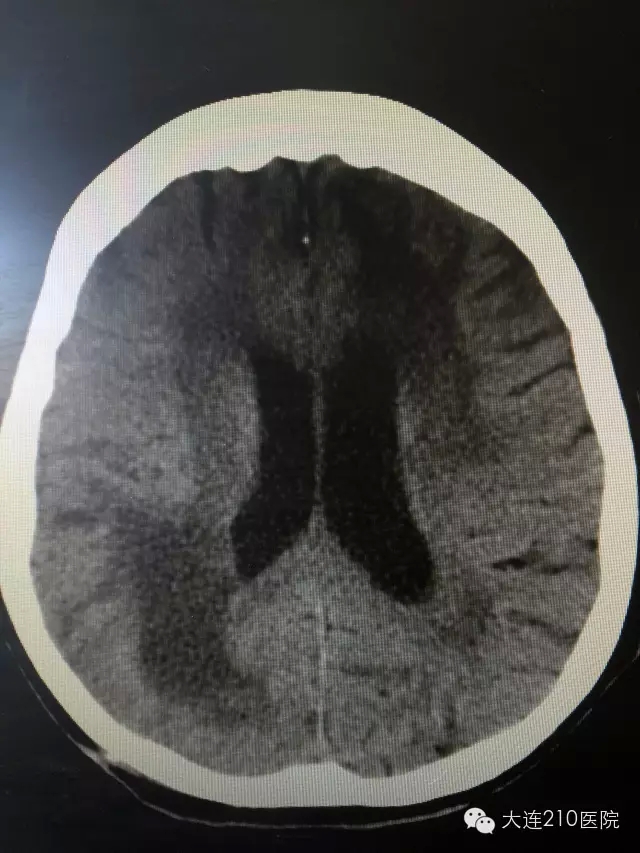

在家属的信任支持下成功施行微创手术,术后第二日,刘老太太便醒来与周围人正常交流,家属喜出望外并对这一技术表示高度认可,经过十余日悉心照顾,病人现已康复出院。

出院前 CT显示颅内血肿彻底消除